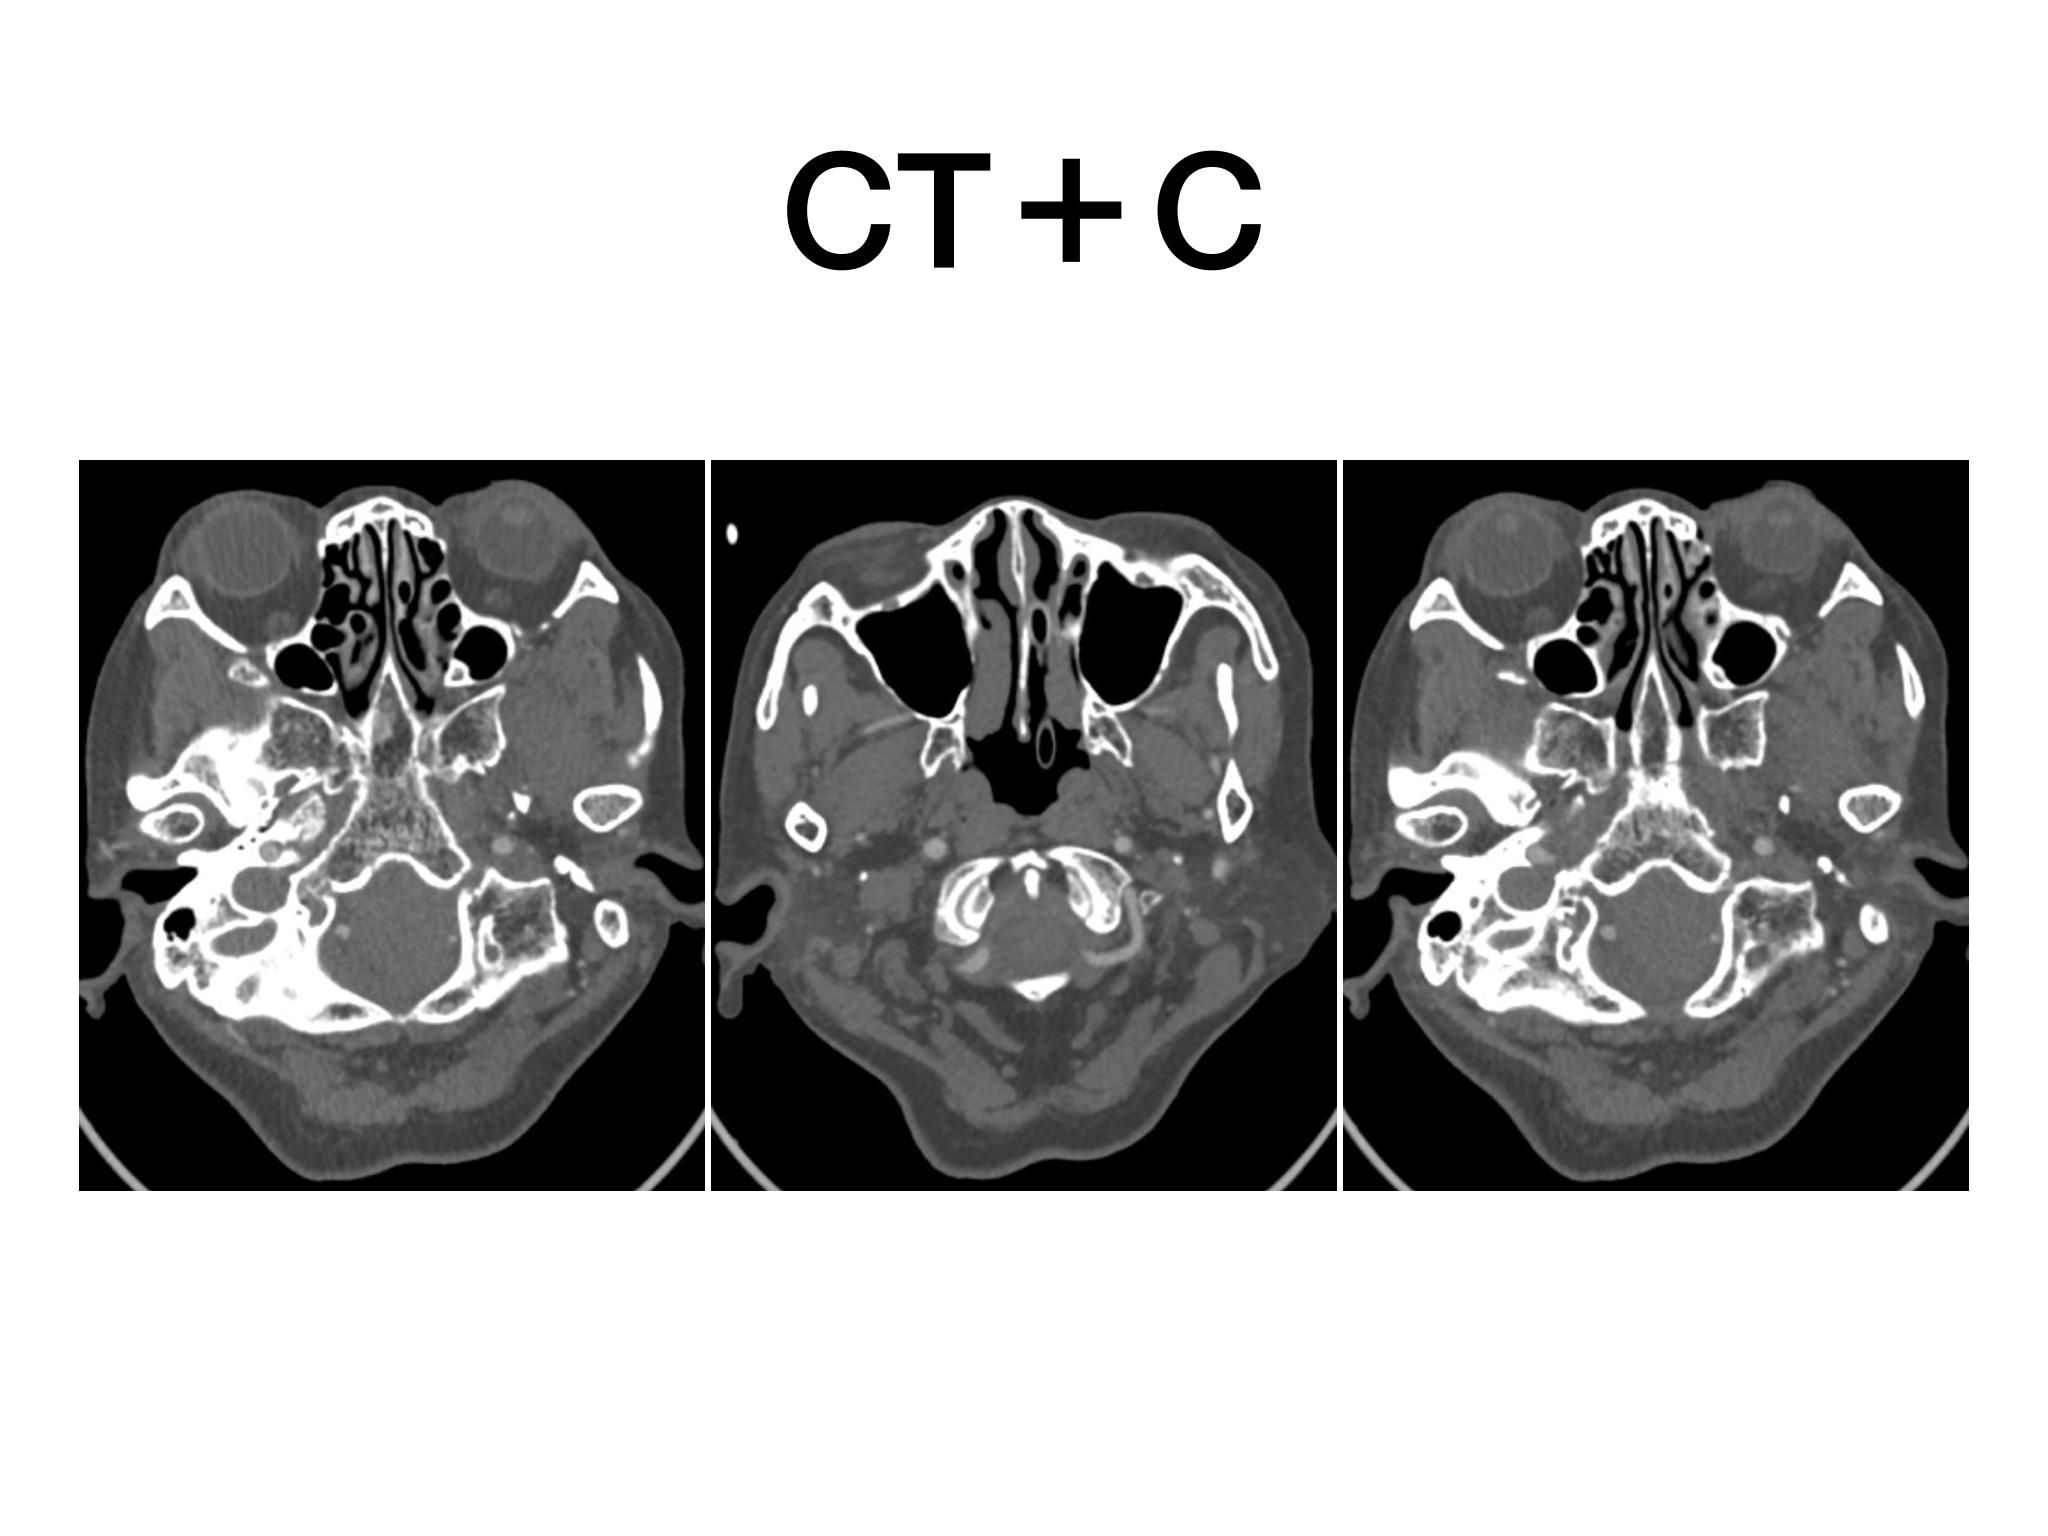

汇报一例后颅底肿瘤手术。为枕骨大孔巨大腹侧型脑膜瘤,该患者高龄,同时合并肺Ca,术前2周急性加重,枕骨大孔疝前期表现,术前已有延髓压迫及后组颅神经麻痹表现。经详细评估后采用远外侧经髁窝入路,最大化显露,重点保护延髓、后组颅神经,尽可能“零骚扰”。术中肿瘤质地韧,血供一般,与肿瘤上极与后组颅神经黏连紧密,最终99%切除,残留约1%,术后顺利康复出院,无新发症状,为后续进行肺部病变化疗创造有利条件。